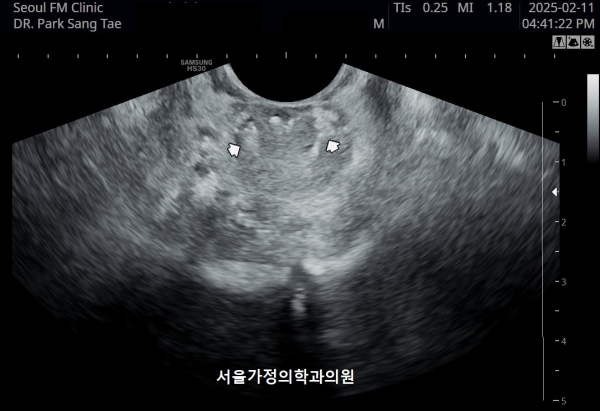

10년전부터 배뇨장애와 빈뇨로 비뇨기과에서 약을 복용중 2년전부터 급박뇨와 요실금이 심해져 투약을 했으나 증상의 호전이 없다고 내원당일 검사한 경직장 전립선 초음파 검사상 전립선 비대와 전립선의 낭종과

사정관주위의 결석이 관찰되는 경직장 전립선 초음파 사진입니다.

This is a transrectal prostate ultrasound image taken on the day of the visit. The patient had been taking medication for urinary difficulties and frequent urination for over 10 years at a urology clinic. However, since two years ago, symptoms of urgency and urinary incontinence worsened despite continued medication. The ultrasound shows prostate enlargement, cysts within the prostate, and calcifications around the ejaculatory ducts.